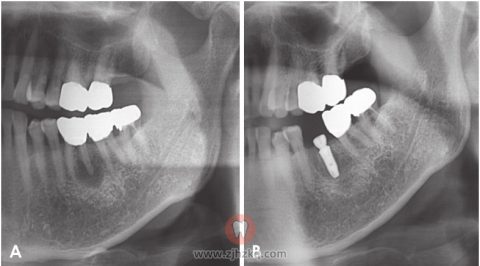

一名43岁的男性在7个月前第一次注意到右下后牙区种植牙周围有伴疼痛的溃疡性病变。他一年前曾接受种植手术。无特殊疾病病史。口腔检查显示种植体周围的牙槽嵴上有伴溃疡的牙龈肿胀,触痛明显。病变部位牙龈发红。全景片显示种植体周围骨破坏,界限不清(图6A),根尖片显示软组织影增大(图6B)。B超表现为边界清楚的不均匀肿块(30 mm×15 mm),可见局限性骨破坏(图7A)。彩色多普勒超声显示,新形成的血管供应肿块的内部和周围(图7B)。活检显示,牙槽嵴粘膜溃疡是恶变引起的上皮完整性丧失所致(图8A)。增生异常的鳞状细胞侵入下层结缔组织,可见明显的炎性细胞浸润。单个肿瘤细胞表现出核多形性、突出的核仁和异常的有丝分裂(图8B),部分癌巢内形成角蛋白珠。根据这些影像学和组织病理学结果,最终诊断为高分化的口腔鳞状细胞癌。

图6.全景片显示,种植体周围有边界不清的骨质破坏。根尖片显示增大的软组织影。